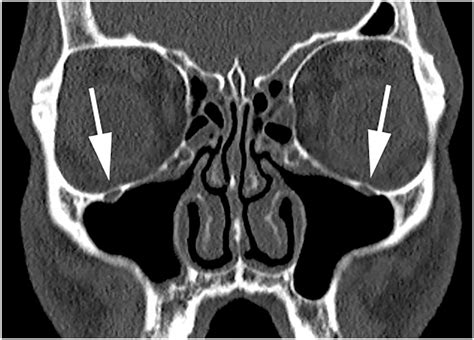

Discovering that you have a Cyst Sinus Maxillaris, commonly known as a maxillary sinus cyst, can be an unsettling experience. Often, these findings occur incidentally during routine dental X-rays or panoramic scans taken for other oral health reasons. While the word "cyst" may sound alarming, understanding the nature of these formations is the first step toward managing your health with peace of mind. A maxillary sinus cyst is generally a fluid-filled sac that develops within the maxillary sinus, which is the air-filled space located behind your cheekbones and above your upper teeth.

A Cyst Sinus Maxillaris is a benign, non-cancerous growth. In clinical terms, they are frequently classified as either mucous retention cysts or pseudocysts. These cysts are typically lined with sinus mucosa and filled with fluid. They do not behave like aggressive tumors, meaning they do not invade surrounding tissues or spread to other parts of the body. In most cases, they are asymptomatic, meaning they do not cause any noticeable pain or physical symptoms.

Since these cysts rarely present with overt symptoms, diagnosis is almost always achieved through imaging. When your dentist or ENT specialist identifies a potential Cyst Sinus Maxillaris, they will use advanced imaging technology to differentiate it from other, more serious pathologies.